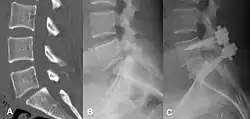

Degenerative spondylolisthesis at L5-S1.

(A) CT sagittal view of a low grade slip.

(B) Lateral radiograph pre-operative intervention.

(C) Surgically treated with L5–S1 decompression, instrumented fusion and placement of an interbody graft between L5 and S1.